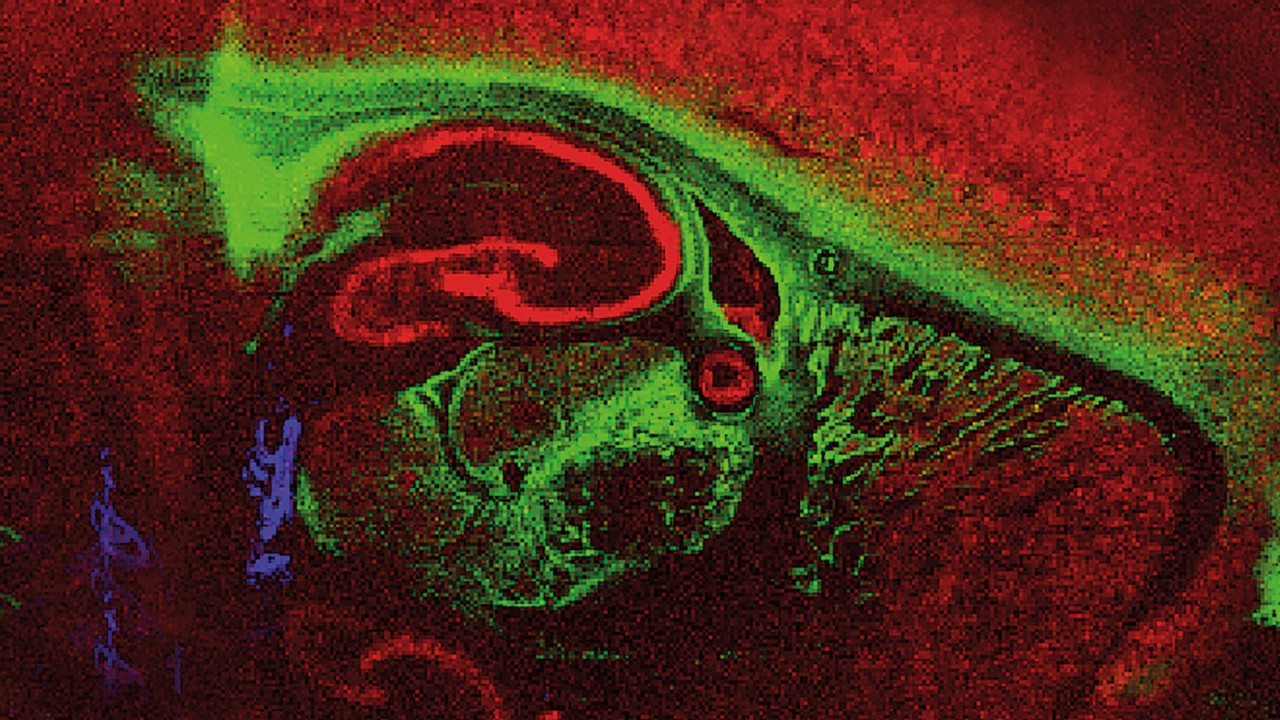

Innovations such as Trapped Ion Mobility (TIMS), smartbeam and scanning lasers for MALDI-MS Imaging that deliver true pixel fidelity, and eXtreme Resolution FTMS (XR) technology capable to reveal Isotopic Fine Structure (IFS) signatures are pushing scientific exploration to new heights. Our mass spectrometry solutions enable scientists to make breakthrough discoveries and gain deeper insights.

Bruker's product lines include the following technologies: timsTOF, MRMS, rapifleX® MALDI-TOF/TOF, UHR-QTOF, Triple Quadrupole, HDX Solution, and TargetScreener HR. Our industry leading software solutions such as SCiLS™ Lab for MS Imaging, MetaboScape® and Biopharma Compass® are examples for our solutions doing the work for you.